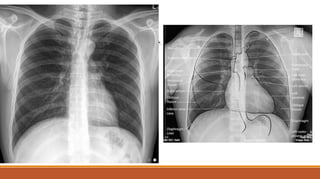

●Chest Xray- PA View

CXR-PA VIEW

NORMAL CXR-PA VIEW

Chest X-ray showing indistinct cardiac borders and bilateral

reticulonodular shadowing suggestive of pulmonary fibrosis.

Initial investigations andfindings Chest X-ray showing indistinct cardiac borders and bilateral reticulonodular shadowing suggestive of pulmonary fibrosis.